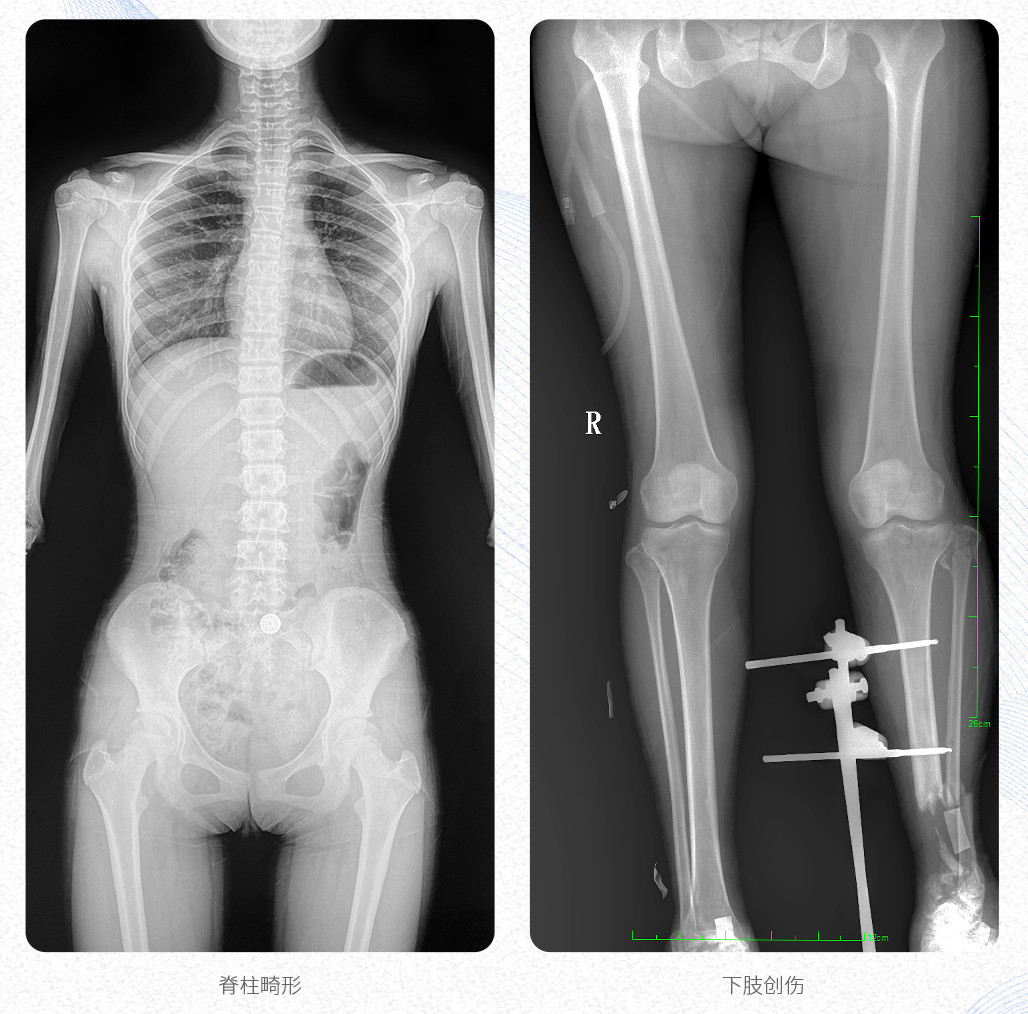

臨床應(yīng)用:支持全脊柱攝影、雙下肢攝影、脊髓造影、復(fù)雜創(chuàng)傷、人工關(guān)節(jié)置換、關(guān)節(jié)損傷的修復(fù)重建等大視野臨床應(yīng)用。

17"*34"有效視野,是市面大尺寸平板的2倍,一次成像不拼接。相較于多張攝影再軟件拼接的DR設(shè)備,PLX8600解決了拼接圖像存在密度不均勻,拼接處圖像配準(zhǔn)和放大效應(yīng)等問題,給臨床帶來了真正的大視野影像解決方案,高清畫質(zhì),準(zhǔn)確成像不失真,可一次性覆蓋全脊柱或雙下肢影像。PLX8600大視野平板動態(tài)DR攝影速度快,患者可以更快的完成檢查,且單次攝影輻射劑量是常規(guī)多張攝影再軟件拼接DR的1/2或1/3,低劑量給患者更多關(guān)愛。

PLX8600大視野平板動態(tài)DR可在低輻射劑量下獲得患者站立位、臥位的高質(zhì)量影像。搭載自主研發(fā)的圖像均衡處理系統(tǒng),能夠很好的均衡人體不同厚度組織的影像,視野大,圖像清晰,層次豐富。